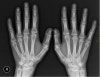

1. X-ray를 찍고 나서 "뼈에는 이상 없어요."라는 말을 자주 듣게 됩니다.

뼈에 이상은 없지만 뼈에서 기인한 통증이 아니기 때문에 통증은 지속됩니다.

이런 경우 X-ray에 나타나지 않는 연부조직의 이상을 찾아 치료해야 합니다.

어차피 X-ray로 찾을 수 없는 연부조직으로 인한 통증이라면 X-ray는 찍을 필요가 없습니다.

물론 X-ray의 경우 방사선 피폭량은 미미한 수준이지만 진단적 가치가 없는 경우 괜히 방사선에 노출될 이유는 없겠습니다.